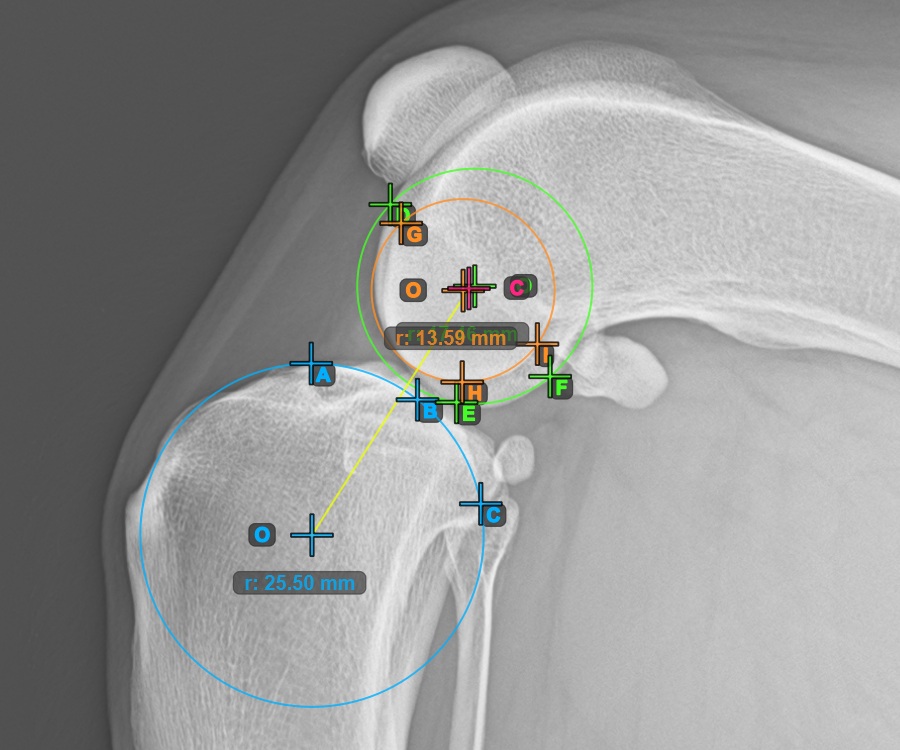

Markieren Sie zusätzlich die drei Punkte auf der Gelenkfläche des zweiten Condylus Femoris.

Markieren Sie die drei Punkte am inneren (sekundären) Kondylus des Oberschenkelknochens (Condylus Femoris). Unabhängig von der Reihenfolge stellen Sie sicher, dass Sie den vordersten Punkt, den hintersten Punkt und den Mittelpunkt des Condylus Femoris markieren. Basierend auf den drei gesetzten Punkten wird automatisch ein Kreis konstruiert.

Das Bild unten zeigt die typische Platzierung der drei Punkte am zweiten Condylus Femoris.